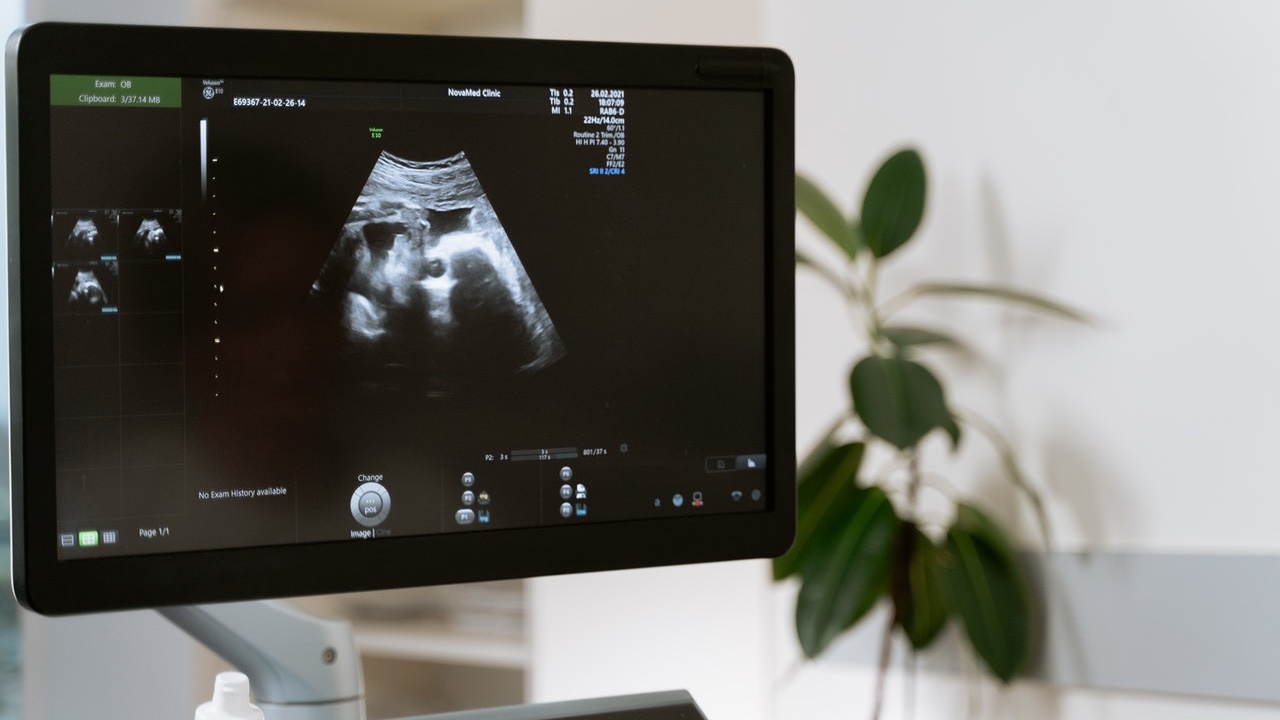

Se trata de una condición en el organismo femenino que no da señales o manda síntomas que se pueden confundir fácilmente con otros padecimientos; inclusive en algunos casos a pesar de hacer ultrasonidos, exámenes de sangre o análisis de orina. También se le conoce como gestación silenciosa.

A pesar de los ultrasonidos, pruebas o análisis, no saben que están embarazadas | Fuente: @Pexels